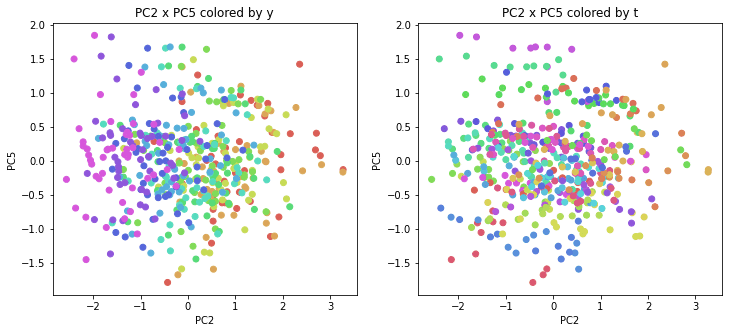

PCAの結果の第n主成分をPCnと表記します。

医療費データの場合と同様に、PCAの結果を見やすく表示するため、seabornのカラーパレットを使って、年月別、都道府県別に色分けして図示してみます(左側が年月別に色分け、右側が都道府県別に色分け)。PC1~PC8まで表示しました。

医療費データの場合ほどはっきりとはしていませんが、PC2が概ね時間の経過を表す成分で、残りの成分が時点によって変わらない地域の特徴を表す成分となっているようです。

また、PC1×PC3を見ると、47沖縄が他の都道府県からかなり離れたところに位置しており、沖縄の地域差が際立っているのが分かります。これは、以前別の記事で年齢階級のない健診データでPCAを実行した場合と似た結果となっています。

今回は、医療費データと同様に、健診データ240次元についてPCAを実行してみました。PCAの結果、医療費データの場合ほどはっきりしとはしていませんが、第2主成分が概ね時間の経過を表す成分で、時間軸に沿った全体的な動き(全国的な動き)を表しており、それ以外の成分が地域の特徴を表す成分で、この10年間あまり変わっていないことがわかりました。